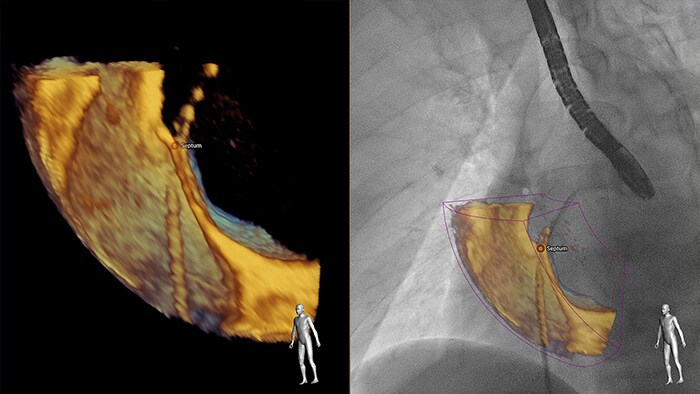

Mayor conocimiento y confianza en la búsqueda y el tratamiento del problema a través de SmartFusion. EchoNavigator se fusiona, de forma automática, con la ecocardiografía transesofágica (ETE) 3D en vivo y rayos X en vivo, en tiempo real, para que pueda guiar intuitivamente su dispositivo en el espacio 3D con mayor rapidez.